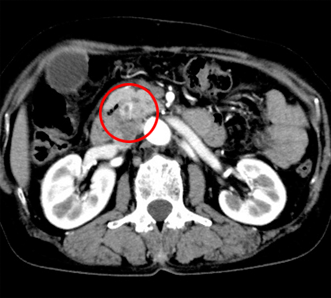

バリウムなどの造影剤を使用して体内臓器の形態、機能をリアルタイムに映像として観察することができます。

平面検出器(FPD:Flat Panel Detector)を搭載したX線TVを使用しているため、高画質で被ばくの少ない検査、治療が行えます。

多目的デジタルX線TV装置を用いた胆道系検査・治療、肝腫瘍に対する血管造影検査・治療等を医師、看護師とともにチームで取り組んでいます。